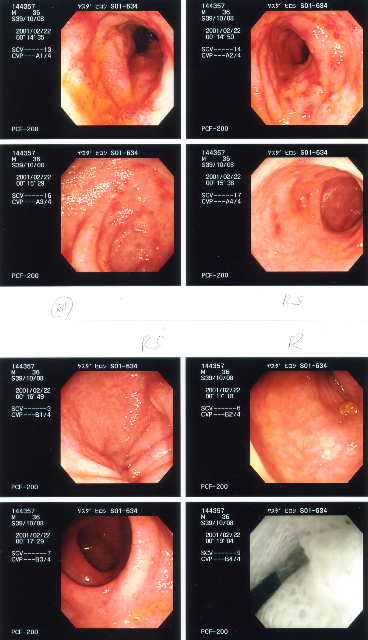

2001/2/22 大腸カメラ   下血も止まり、CRP値の0.0の時期。直腸、S状結腸の炎症はほとんど治まっているが、下行結腸、横行結腸に炎症が残っている(らしい)。食事は、この炎症がおさまってからとの事。